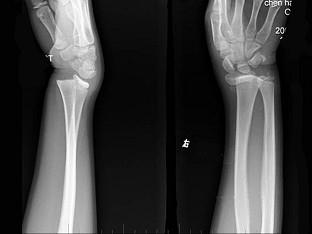

根据所提供图像,选择最佳选项 ( )A、舟骨骨折B、骺离骨折C、Smith骨折D、未见异常E、Colles骨折

选项 A、舟骨骨折 B、骺离骨折 C、Smith骨折 D、未见异常 E、Colles骨折

答案 B